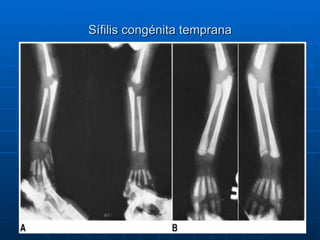

Clasificación de la sífilis congénita según el momento de aparición de los síntomas La mayoría de los neonatos con sífilis son asintomáticos Sífilis congénita temprana: aparecen antes de los dos años de edad Sífilis congénita tardía: aparecen después de los dos años de edad

Diagnóstico de sífilis congénita Examen físico VDRL o RPR en suero Radiografía de huesos largos Hemograma y recuento de plaquetas En LCR: VDRL, leucocitos y proteínas Neurosífilis:  -VDRL reactivo en cualquier dilución -Proteínas  > 150 mg/dl en neonato ó > 40 mg/dl en mayores de 1 mes -Leucocitos:>25/mm 3  en neonatos ó > 5 /mm 3  en mayores de 1 mes FTA-Abs: No es necesario